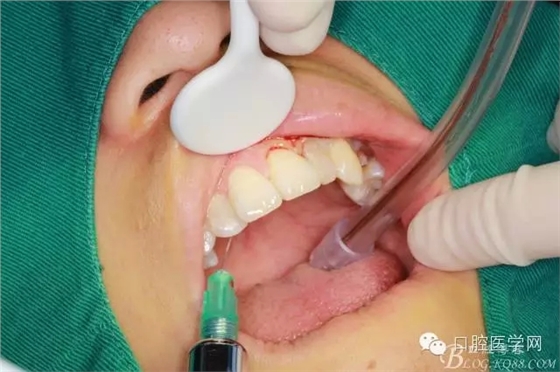

術(shù)前口內(nèi)照

常規(guī)口內(nèi)外消毒鋪巾

局部浸潤麻醉

齦乳頭麻醉

鼻腭神經(jīng)麻醉